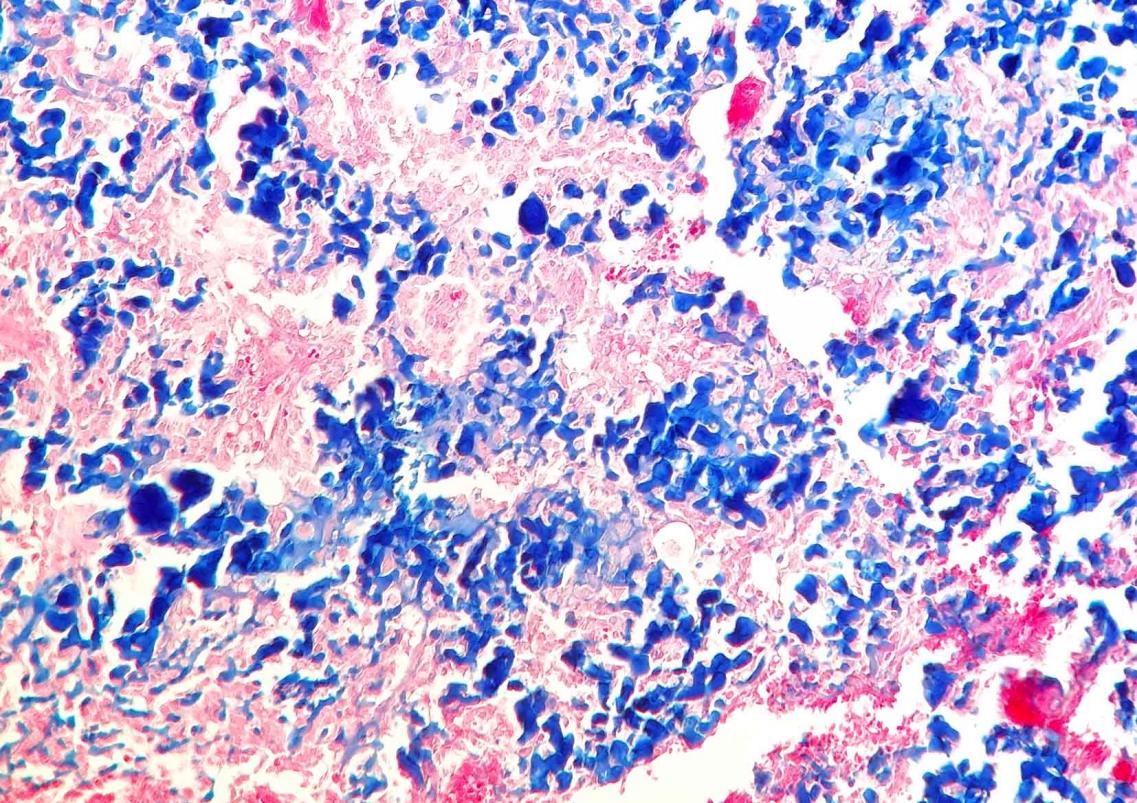

Este estudio retrospectivo fue encaminado por Celic Berenice Montoya, estudiante de especialidad del Departamento de Patología de la Facultad de Veterinaria de la prestigiosa UNAM de México, durante su rotación en Noah's Path en 2017. En el mismo, publicado recientemente en la Revista de Clínica Veterinaria de Pequeños Animales de AVEPA, se describen 6 casos de condrosarcoma en cobayas con predilección por huesos planos y, en 3 de los pacientes, metástasis. Los condrosarcomas se observan en cobayas con mayor frecuencia que en el resto de mamíferos exóticos, en los que son muy raros.